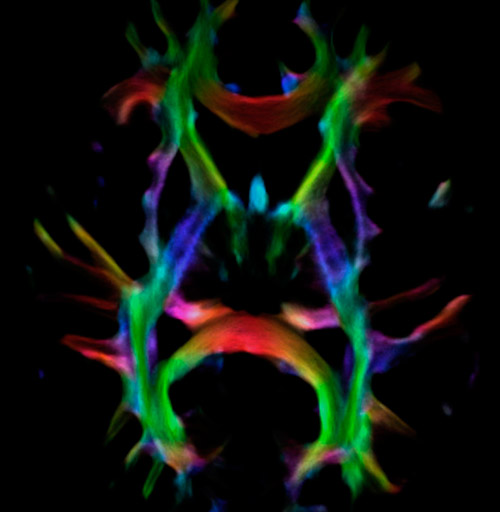

Super-resolution directionally encoded color track-density imaging overlaid on T1-weighted structural MRI.